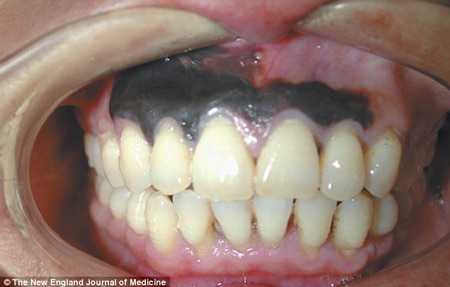

(VTC News) - Người đàn ông này có lợi chuyển sang màu đen được chẩn đoán bị u ác tính ở miệng.

Theo các bác sỹ, vùng đen trên lợi của quý ông này rộng khoảng 1.5cm x 4cm. Trước đó, người đàn ông 45 tuổi bị ung thư hoàn toàn khỏe mạnh và không có bất kỳ đau đớn nào.

Chỉ vì lợi chuyển màu đen nên ông ta mới tìm đến các bác sỹ.

Người đàn ông Trung Quốc được chẩn đoán mắc căn bệnh ung thư rất hiếm gặp. Đây là căn bệnh ung thư niêm mạc. 50 % các trường hợp xảy ra ở các vị trí trên đầu hoặc cổ.

| Lợi của người đàn ông bị ung thư. (Ảnh: Dailymail) |